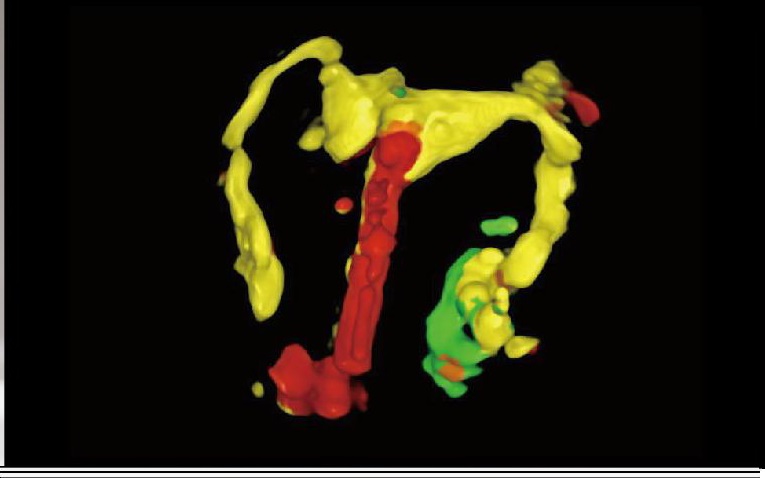

HyCoSy with SPI

Histerosalpingo Kontrast Ultrasonografi (HyCoSy), rahim yapısında bir anomali olup olmadığını gözlemlemek ve tuba (fallop tüplerinin) açıklığını değerlendirmek için kullanılabilir.